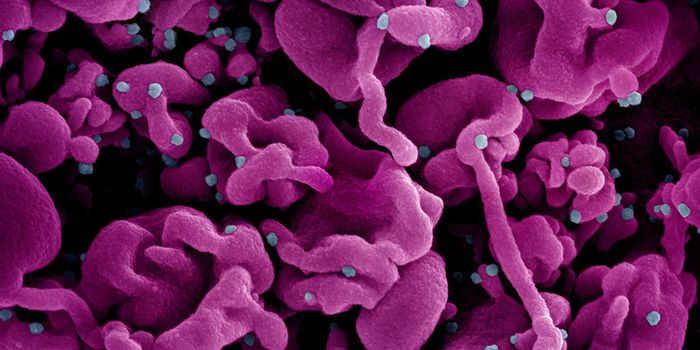

DEC 07, 2021Clinical & Molecular DXMore mutations, more transmissible, and more likely to infect vaccinated people—coronavirus variants such as Omicr ...

AUG 03, 2022Clinical & Molecular DXWith the 2020 Covid lockdowns still fresh in our minds, the recent outbreak of monkeypox in the United States has many p ...